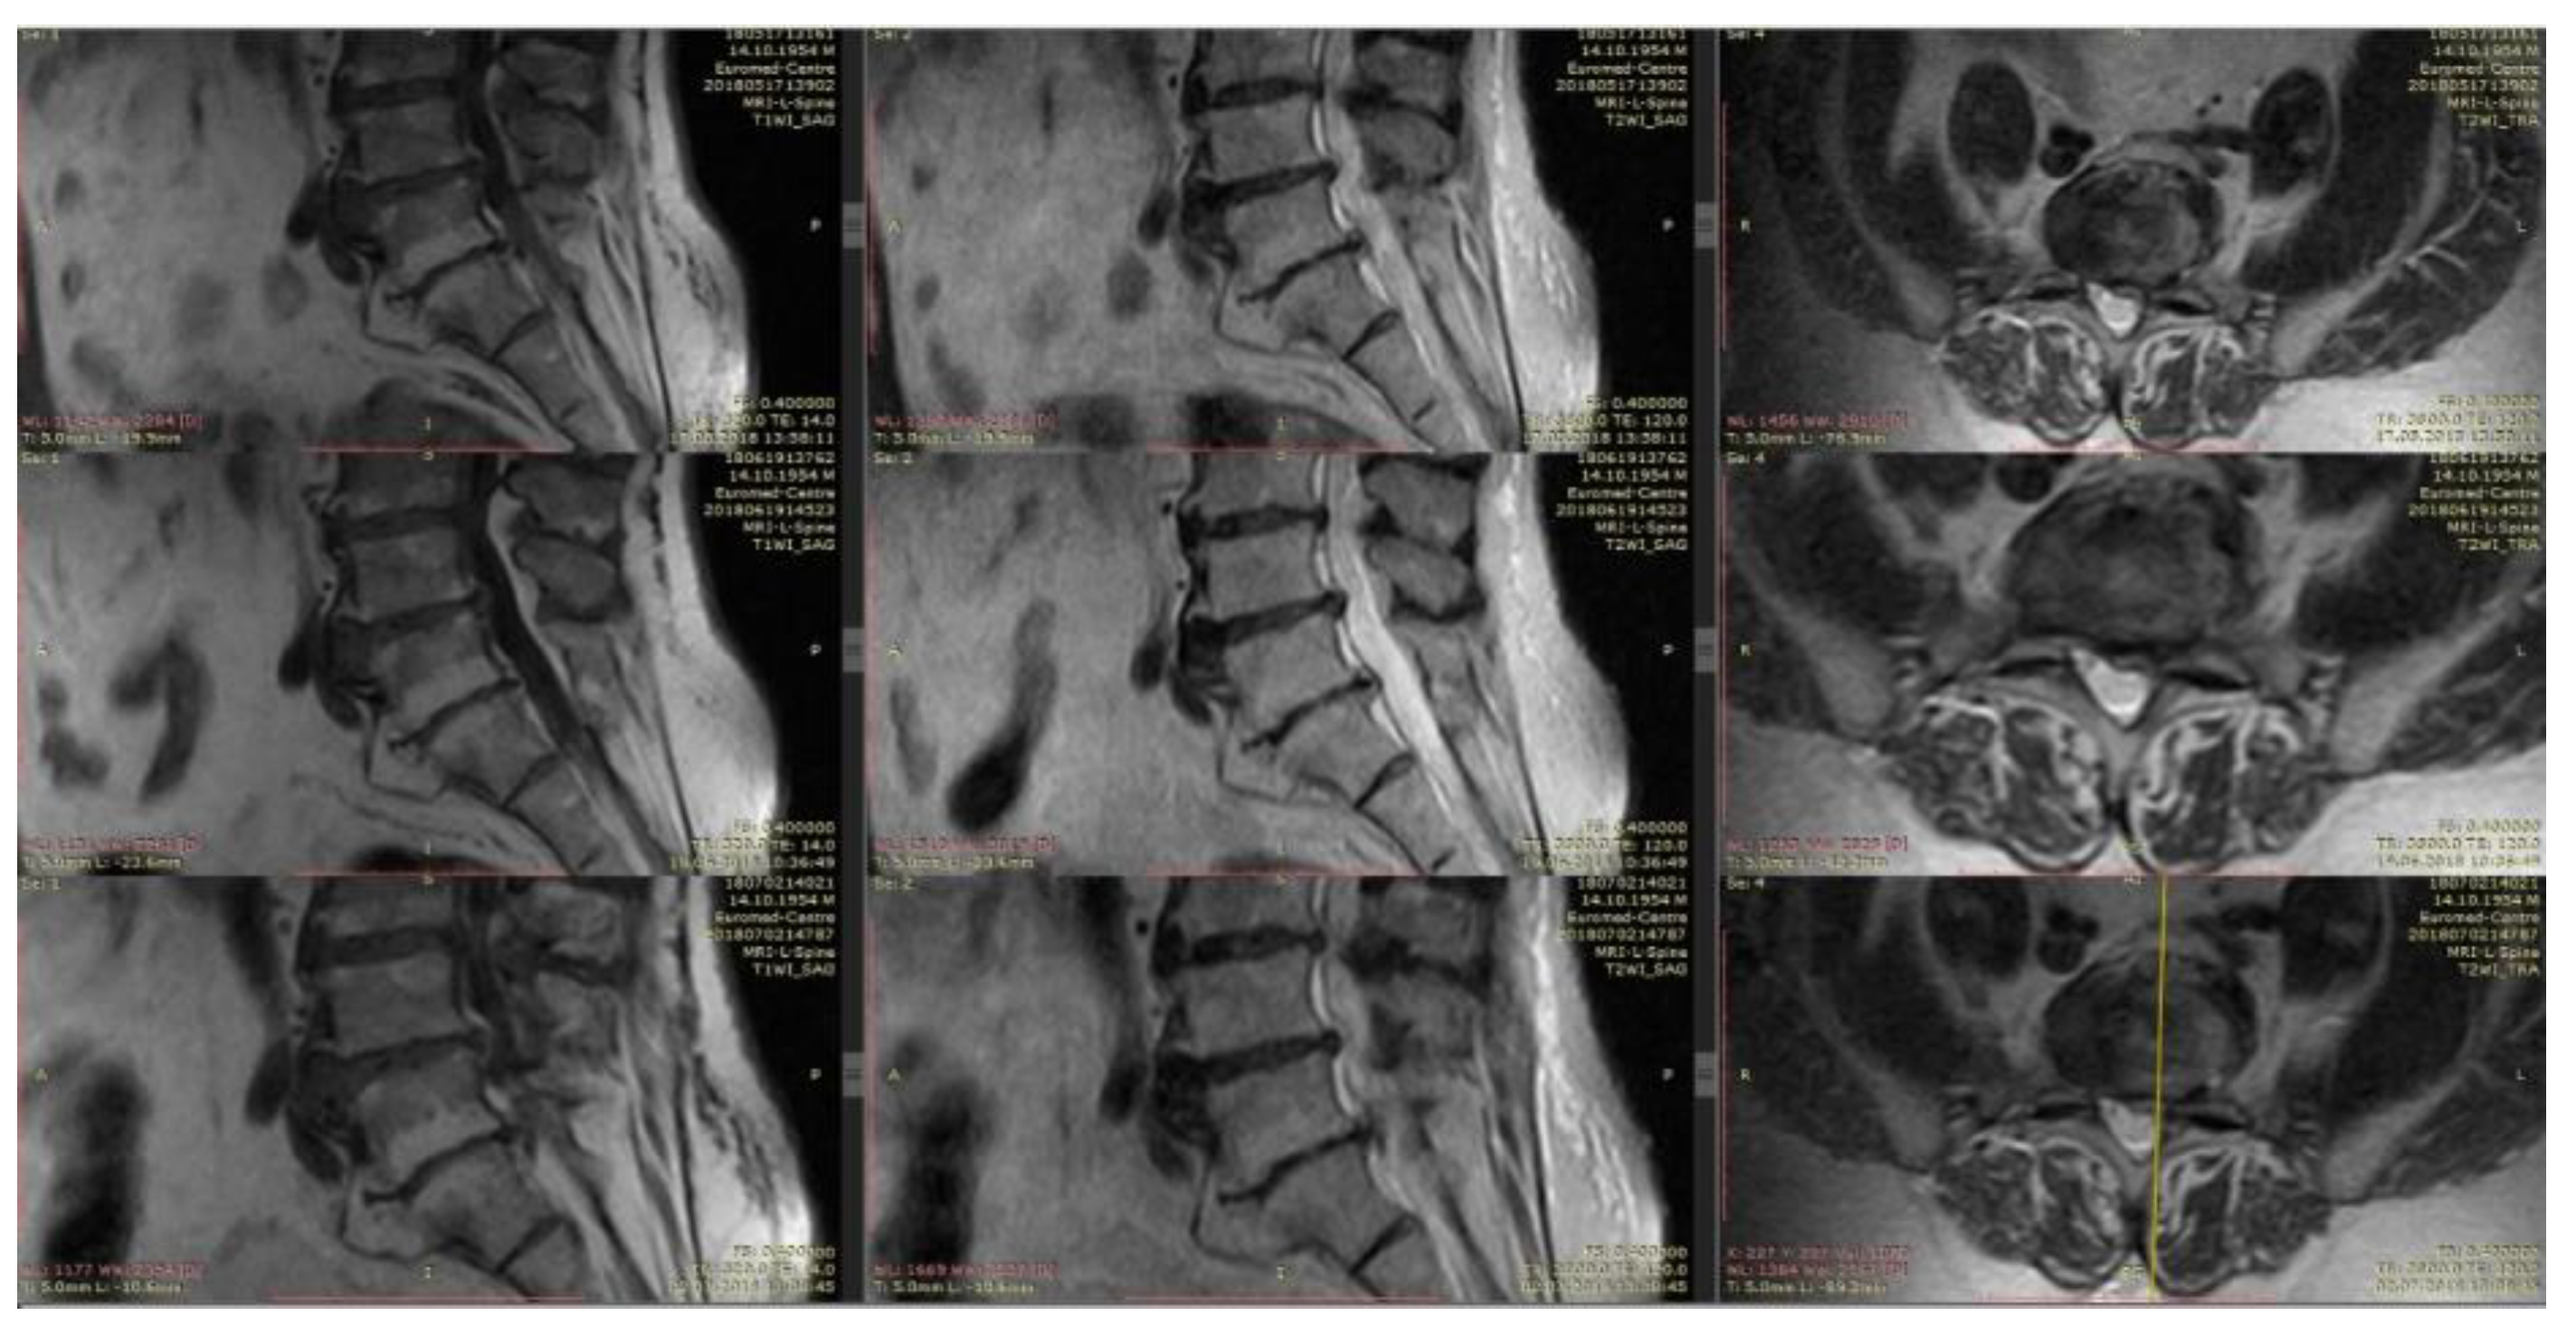

4.4. Clinical Case 3 (L-Lysine Group, 10 mL)

An indicative case that confirms the thesis “big hernias of the disk are most prone to regress” [54].

Patient V., 52 years old, with back pain duration of three days. VAS: 7. The pain extends to the legs, more right, in particular, the anterior-medial parts of the thigh and legs. Hypoesthesia in the dermatome L3, straight leg test 60°. Movements exacerbate the pain.

MRI: Extrusion of the intervertebral disk L2–L3 with compression of foraminal channels bilaterally. At day 30, there was a clear reduction in the size of extrusion, which was accompanied by a clinical “recovery”, a complete regression of pain (Figure 8).

Figure 8. On follow-up T1 and T2-weighted MRI of the lumbar spine, the regressed extruded disc fragment is seen at the L2-3 level and the dural sac is free from compression.